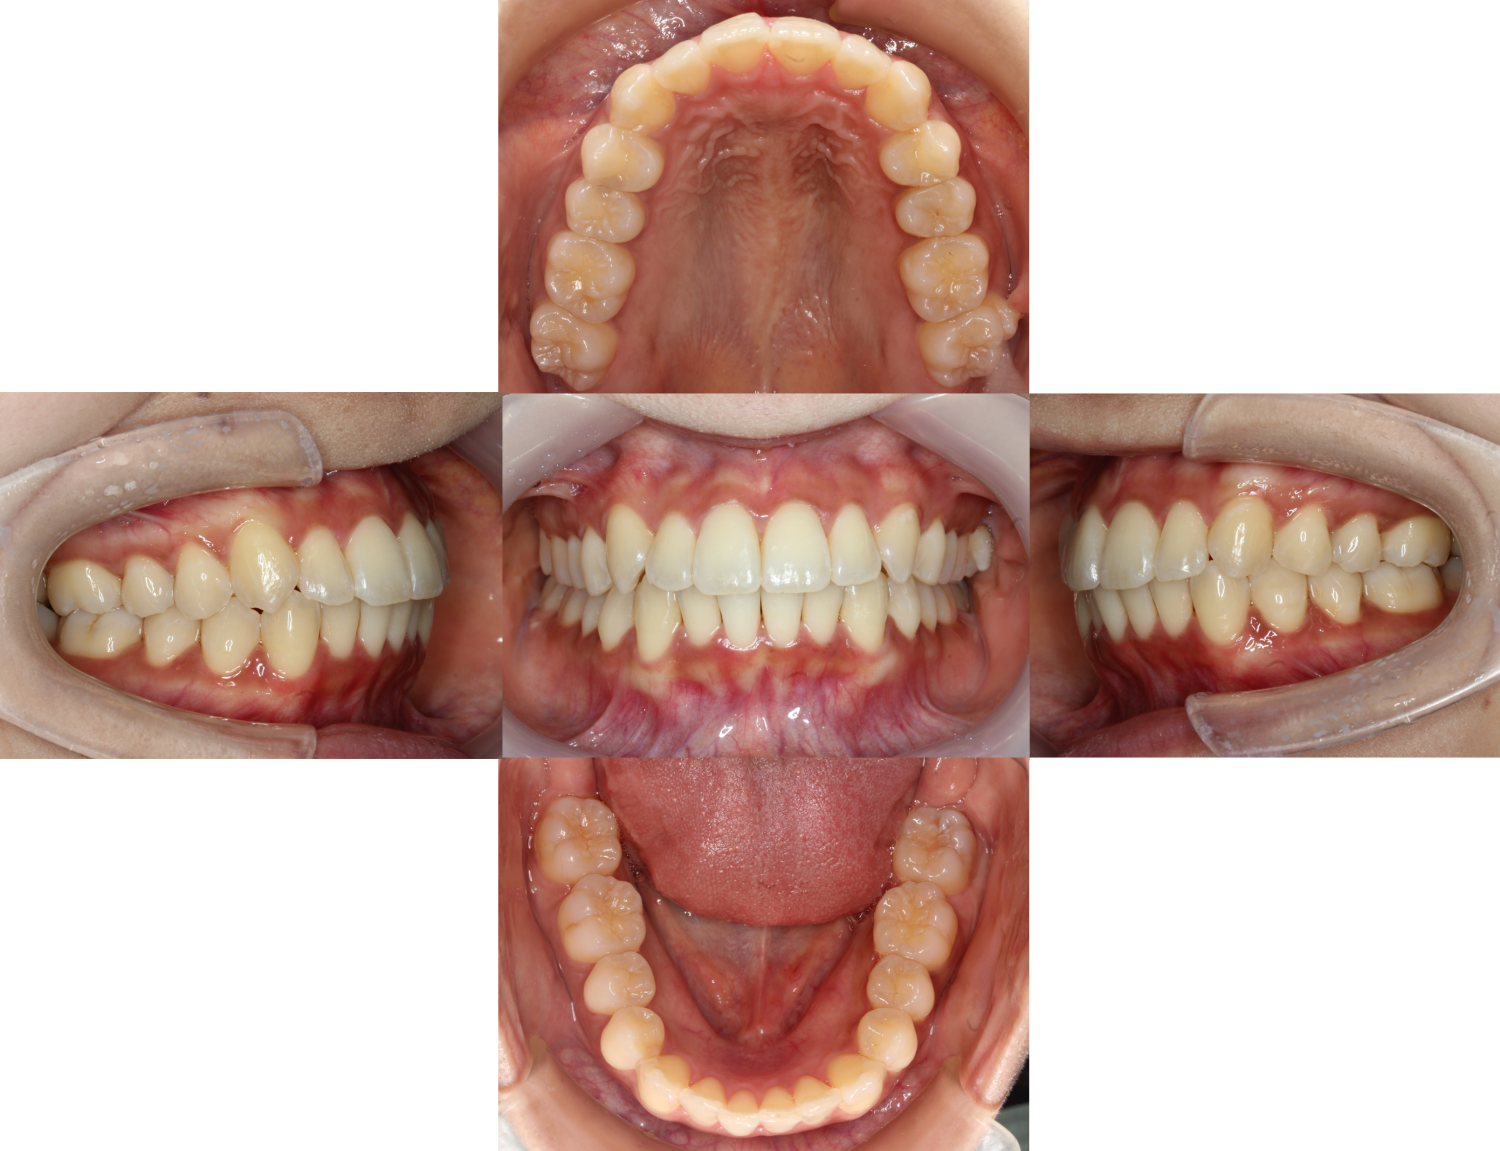

八重歯だった部分がとてもきれいになりました。

残りの微調整はマウスピース矯正で行っていきます。

全体の歯並びが整い、噛み合わせもしっかり噛んでいます。

元々のお悩みだった【八重歯と上下前歯の凸凹】も綺麗に良くなりました。